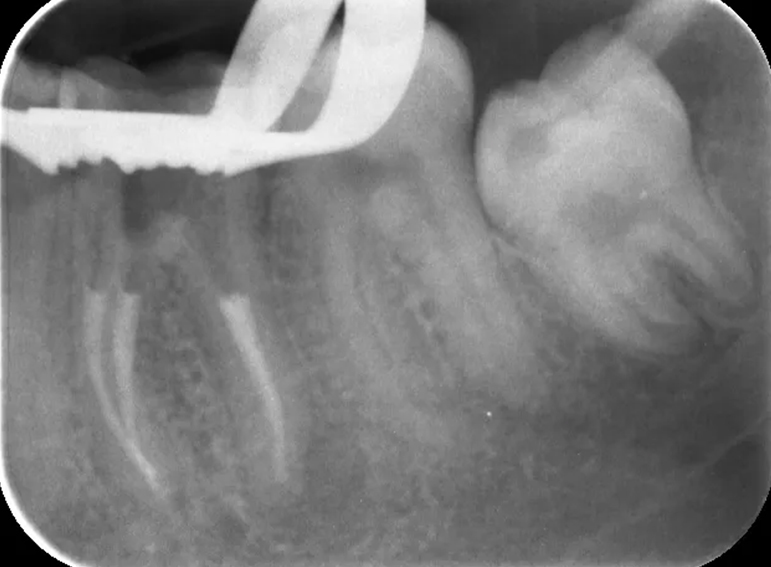

Root filling revision of a lower molar.